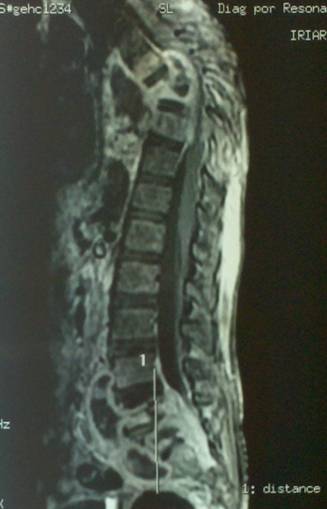

- Figura No 1a

- Figura No 1b

- Figura No 1c

- Figura No 1d

- Figura 1 Texto